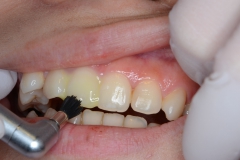

検査1)染め出し検査+記録

一見きれいそうにみえる歯も、

歯垢染色剤を塗布してみると…

こんなに汚れています。まずは、この歯垢をとりのぞきます。

歯面研磨)

専用のブラシとペーストを使い歯のザラザラした面をきれいにしていきます。

ラバーカップと細かい粒子のペーストを使いさらにつるつるに仕上げます